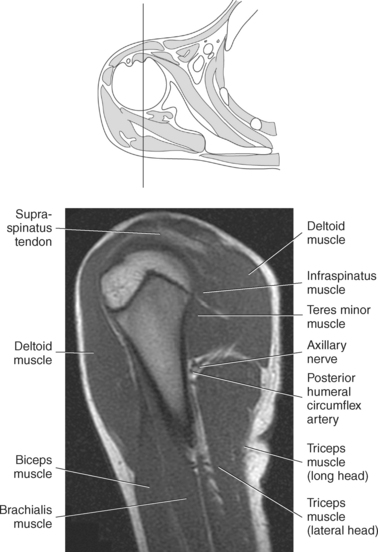

The scapula is a triangular-shaped flat bone that forms the posterior portion of the shoulder girdle. It has a medial margin, a lateral margin, and a superior margin. The margins are separated by the superior, inferior, and lateral angles (Figures 9.2 and 9.3). The anterior surface of the scapula, subscapular fossa, is flat and slightly concave. The posterior surface of the scapula is divided by the scapular spine into a smaller supraspinous fossa, and a larger infraspinous fossa (Figure 9.7). Four projections of the scapula provide attachment sites for the muscles and ligaments contributing to the shoulder girdle. These include the scapular spine, acromion, coracoid process, and glenoid process (Figures 9.7 through 9.10). The scapular spine arises from the upper third of the posterior surface of the scapula and extends obliquely and laterally to give rise to a flattened process termed the acromion. Located on the anterolateral surface of the scapula is a beaklike process termed the coracoid process, which arises just medial to the glenoid process and functions to protect the shoulder joint, which lies beneath it. The coracoid process is an attachment site for the pectoralis minor, short head of the biceps brachii, and the coracobrachialis muscles. The scapular notch is located just medial to the coracoid process, on the superior margin of the scapula and allows for the passage of the suprascapular nerve (Figure 9.2). The glenoid process, the largest of the projections, forms the lateral angle of the scapula and ends in a depression called the glenoid fossa (glenoid cavity) (Figures 9.7 through 9.9). There are two tubercles associated with the glenoid fossa, an upper supraglenoid tubercle and a lower infraglenoid tubercle, which serve as attachment sites for the biceps brachii and triceps brachii (Figure 9.8). The shallow articular surface of the glenoid fossa joins with the relatively large articular surface of the humeral head to create the freely moving glenohumeral joint (Figures 9.2, 9.3, 9.11, and 9.12).

Figure 9.10 Sagittal oblique, T1-weighted MR scan of shoulder.

Key: cor, Coracoid process; cl, clavicle; sup, supraspinatus; ac, acromion; inf, infraspinatus; de, deltoid; tm, teres minor; gl, glenoid; sub, subscapularis; h, humerus; grt, greater tubercle; sc, scapula; glf, glenoid fossa; hh, humeral head.

Muscles of the scapula are described in Table 9.2 and demonstrated in Figures 9.34 through 9.52. The large deltoid muscle originates on the clavicle, acromion, and scapular spine to blanket the shoulder joint as it extends to insert on the deltoid tuberosity of the humerus. This powerful muscle forms the rounded contour of the shoulder and functions primarily to abduct the arm (Figure 9.48). The teres major muscle is a flat rectangular muscle that adducts and medially rotates the arm. It extends from the inferior angle of the scapula to the medial aspect or lip of the intertubercular groove of the humerus (Figure 9.49, A). The four remaining muscles, supraspinatus, infraspinatus, teres minor, and subscapularis, closely surround the scapula and compose the rotator cuff (Figures 9.49 through 9.52). The rotator cuff provides dynamic stability to the shoulder joint and allows for adduction, abduction, and rotation of the humerus. The supraspinatus, infraspinatus, and teres minor muscles are located on the posterior aspect of the scapula. The tendons of these muscles insert on the greater tubercle of the humerus. The supraspinatus muscle lies in the supraspinous fossa of the scapula and helps to abduct the arm. The tendon of the supraspinatus muscle is the most frequently injured tendon of the rotator cuff because of possible impingement as it extends under the acromioclavicular joint and continues over the humeral head (Figure 9.49, B). The infraspinatus muscle is a triangular muscle that lies below the scapular spine in the infraspinous fossa. It acts to laterally rotate the arm (Figure 9.49, A). Lying along the inferior border of the infraspinatus muscle is the elongated teres minor muscle, which also acts to laterally rotate the arm (Figure 9.49, B). The subscapularis muscle is the only muscle of the rotator cuff located on the anterior surface of the scapula; its tendon inserts on the lesser tubercle of the humerus (Figures 9.50 through 9.52). The subscapularis muscle acts to medially rotate the humerus. See sequential images through the shoulder (Figures 9.34 through 9.47).